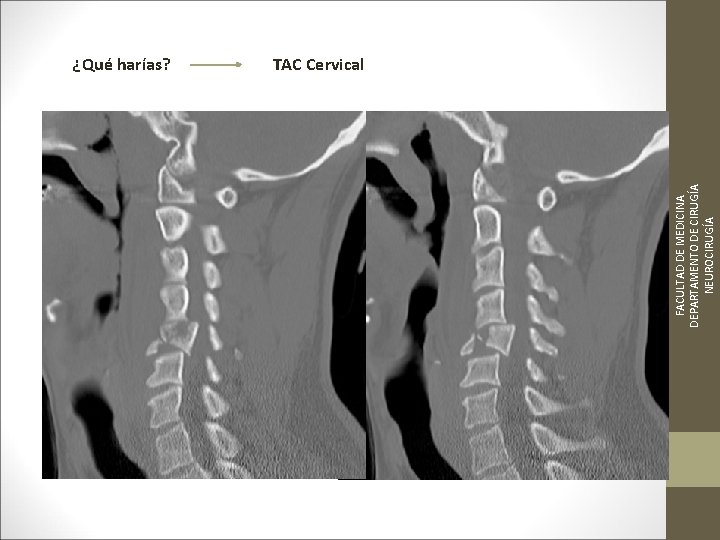

FACULTAD DE MEDICINA DEPARTAMENTO DE CIRUGÍA NEUROCIRUGÍA ¿Qué harías? TAC Cervical

TC Desplazamientos de fragmentos óseos ¿Algo mas? Desplazamientos discales y lesiones ligamentosa FACULTAD DE MEDICINA DEPARTAMENTO DE CIRUGÍA NEUROCIRUGÍA RM